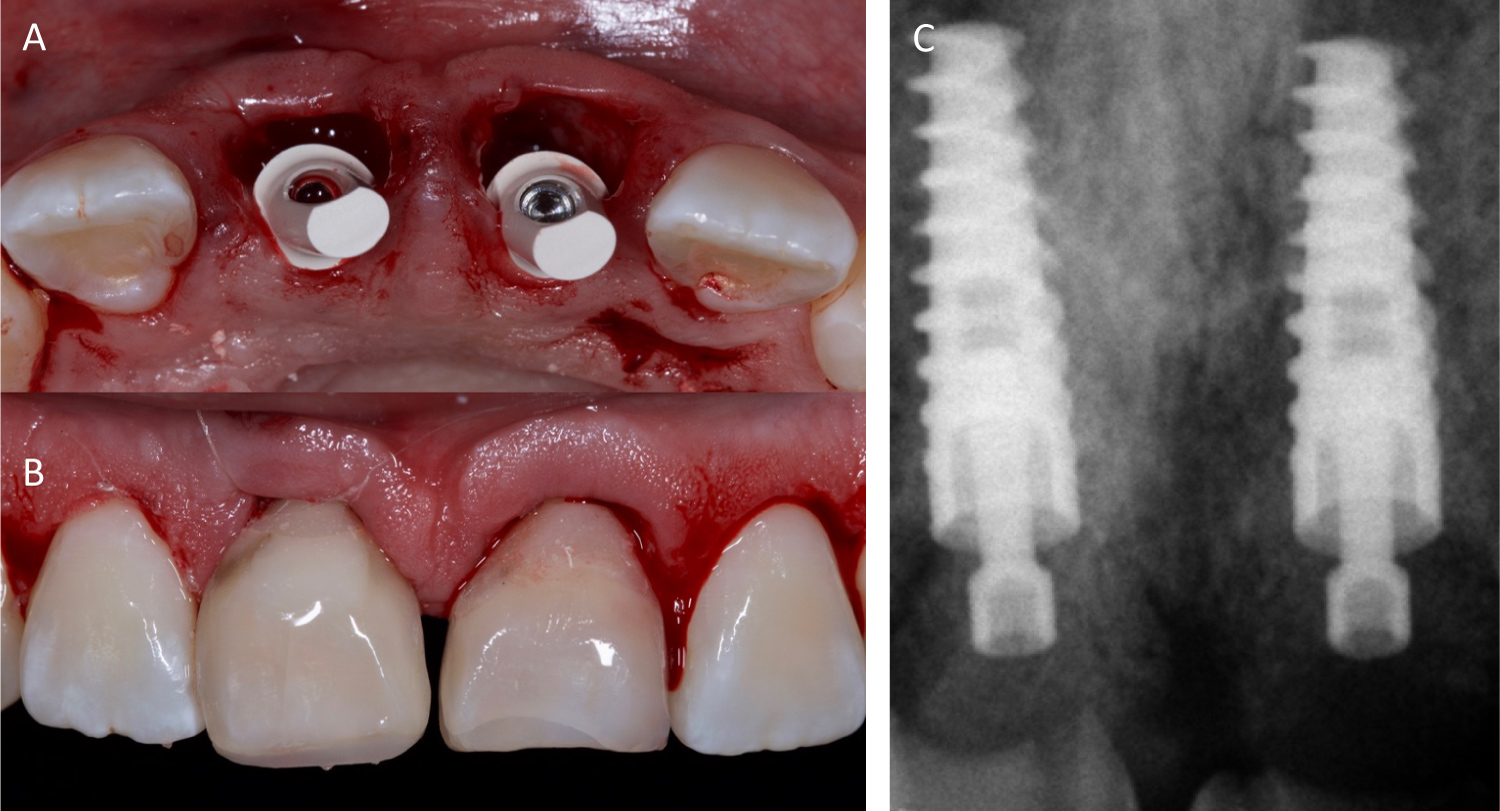

After the teeth were extracted, thorough debridement of the extraction sockets was accomplished using surgical curettes and a Hirschfeld file with copious irrigation (Figure 4).

Figure 4: Post-extraction alveolar socket. View Figure 4

A duplicate of the study model was obtained which was used to fabricate a surgical guide using a 0.80 caliber rigid acetate sheet to perform the drilling protocol at the cingulum level of the adjacent teeth, allowing a three-dimensional positioning of the implant ensuring correct emergence profile and screw access hole for provisional and final restoration. The dental implant system used was ADIN (Touareg™ - OS), two 4.2 × 11.5 mm conical, self-tapping implants were used with an OsseoFix™ surface treatment, a high purity surface with calcium phosphate with a roughness that favors primary stability and increases the implant-bone interface.

The implant insertion was according to the manufacturer's proposed protocol for drilling sequence with a minor modification using one less bur to under prepare the osteotomy site to improve anchorage and primary stability for the implants. The implants were placed in the prepared site toward the palatal wall of the extraction sockets to a depth of 3 mm from the free gingival margin and their final fit was assured to 40N cm and measured the ISQ for each implant. ISQ values for both were ISQ 67, for the right incisor and ISQ 69 for the left incisor (Figure 5).

Figure 5: (A) Surgical guide; (B) Implant placement and parallelism verification; (C) Implant placement and ISQ measurement. View Figure 5

The distance between the implant platform and the marginal soft and hard tissue supported the decision to graft the alveolus using synthetic porous hydroxyapatite 50-50 mixture with autologous bone graft harvested with the burs during the drilling sequence. This graft mixture was placed in the alveolar-implant gap surrounding the implant. (Figure 6).

Figure 6: Guided bone regeneration and implants in place. View Figure 6